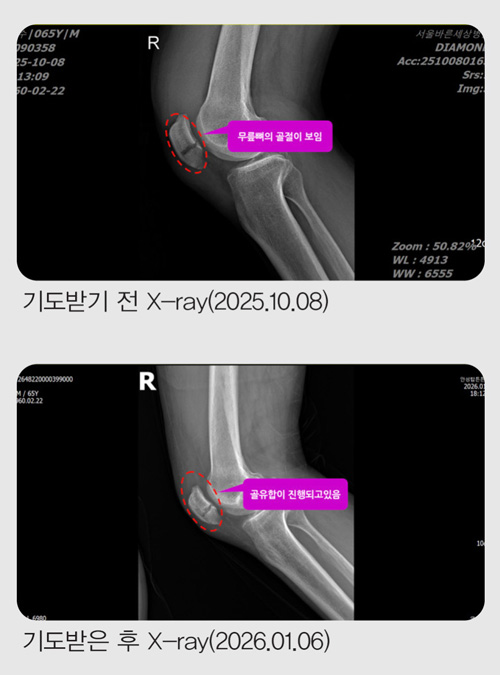

ÀÛ³â 10¿ù 8ÀÏ ¼ö¿äÀÏ, Ãß¼® ¿¬ÈÞ¸¦ ¸Â¾Æ ¸ðó·³ °¡Á·µé°ú ÇÔ²² ºÏÇѻ꿡 ¿Ã¶ú½À´Ï´Ù.

»êÇàÀ» ½ÃÀÛÇÑ Áö ¾à 15ºÐÂë Áö³µÀ» ¶§, »ÏÁ·ÇÏ°Ô Æ¢¾î³ª¿Â µ¹¸æÀÌ¿¡ ¿ÞÂÊ ¹ß¸ñÀÌ °É·Á ³Ñ¾îÁ³½À´Ï´Ù.

´Ù½Ã ÀϾ »êÀ» ¿À¸£·Á ÇßÁö¸¸ ¹«¸À» Â´Â µíÇÑ ±Ø½ÉÇÑ ÅëÁõ¿¡ ´õ ÀÌ»ó ÇÑ ¹ß¦µµ ¿òÁ÷ÀÏ ¼ö ¾ø¾î °á±¹ »êÀ» ³»·Á¿Í¾ß Çß½À´Ï´Ù. ³»·Á¿À´Â ±æÀº »êÇຸ´Ù ÈξÀ ´õ °íÅ뽺·¯¿ü½À´Ï´Ù. µÎ ¼ÕÀ» ¹Ù´Ú¿¡ ¤°í °è´ÜÀ» ÇÑ °è´Ü¾¿, ÇÑ ¹ß·Î °£½ÅÈ÷ ³»·Á¿Í °Ü¿ì Åýÿ¡ ¸öÀ» ½ÇÀ» ¼ö ÀÖ¾ú½À´Ï´Ù.

Åýà ¾È¿¡¼ ¹«¸À» ¸¸Áö´Â ¼ø°£, »À°¡ ºÎ·¯Á³´Ù´Â °ÍÀÌ ºÐ¸íÈ÷ ´À²¸Á³½À´Ï´Ù.

Áý ¾Õ¿¡ µµÂøÇßÁö¸¸ ÇÑ ¹ß¦µµ °È±â Èûµé¾î ´Ù½Ã Åýø¦ Ÿ°í ±Ùó °³ÀÎ º´¿øÀ¸·Î °¬°í, °ð¹Ù·Î Å« º´¿ø ÀÀ±Þ½Ç·Î À̵¿Ç϶ó´Â ¸»À» µé¾ú½À´Ï´Ù.

ÀÀ±Þ½Ç¿¡¼ MRI¸¦ ÃÔ¿µÇÑ µÚ, ÀÇ»ç ¼±»ý´ÔÀº "¹«¸»À°¡ °ñÀýµÆ½À´Ï´Ù. ¹«¸Àº ÀÏ¹Ý »À¿Í ´Þ¸® À§¾Æ·¡°¡ ºÐ¸®µÅ ÀÖ¾î ¹Ýµå½Ã ¼ö¼úÀÌ ÇÊ¿äÇÕ´Ï´Ù"¶ó°í ¸»Çß½À´Ï´Ù.

ÀÌ¾î ¼ö¼úÀ» ÇÏ´õ¶óµµ ¸ñ¹ß »ç¿ë°ú ÀçȰ Ä¡·á°¡ ÇÊ¿äÇÏ´Ï 10¿ù 10ÀÏ ±Ý¿äÀÏ¿¡ ¼ö¼úÀ» ÇÏÀÚ°í ±ÇÇß½À´Ï´Ù.

±×·¯³ª ÀÔ¿øÇØ ¼ö¼úÀ» ¹Þ°Ô µÇ¸é 10¿ù 12ÀÏ¿¡ ÀÖ´Â ±³È¸ ⸳ 43Áֳ⠱â³ä ¿¹¹è¿¡ Âü¼®ÇÒ ¼ö ¾ø¾ú½À´Ï´Ù. Àú´Â ¹ÏÀ½À¸·Î Ä¡·á¹Þ°íÀÚ ÀÔ¿øÀ» ¼±ÅÃÇÏÁö ¾Ê°í ÁýÀ¸·Î µ¹¾Æ¿Ô½À´Ï´Ù.

Áý¿¡ µ¹¾Æ¿Â µÚ ´Ù´Ï¿¤ ö¾ß±âµµÈ¸ ¶§¸¶´Ù Á÷ÀåÀ̳ª Áý¿¡¼ ÈÆòÀ» ÁÀÁö ¸øÇß´ø Á¦ ¸ð½ÀÀ» ±íÀÌ È¸°³ÇÏ¸ç ±âµµÇß°í, À̼öÁø ¸ñ»ç´Ô²²¼ ÇØÁֽô ȯÀÚ¸¦ À§ÇÑ ±âµµ¸¦ ¸ÅÀÏ ¹Þ¾Ò½À´Ï´Ù.

10¿ù 12ÀÏ ±³È¸ ⸳ ±â³ä ÁÖÀÏ ´çÀÏ, ¹«¸ ÅëÁõÀÌ ½ÉÇØ ¹ßÀ» µðµô ¶§¸¶´Ù ÈûÀÌ µé¾î ÈÙü¾î¸¦ ÁغñÇÑ Ã¤ À̸¥ ½Ã°£¿¡ Çà»çÀå 1Ãþ ·Îºñ¿¡ µµÂøÇß½À´Ï´Ù. Çà»çÀå¿¡ µé¾î°¡½Ã´ø À̼öÁø ¸ñ»ç´Ô²²¼ Àú¸¦ º¸½Ã°í ¸ñ·Ê·Î ÀλçÇØ Á̴ּµ¥, ±× ¼ø°£ ¼³¸íÇÒ ¼ö ¾ø´Â Æò¾ÈÀÌ Á¦ ¸¶À½À» °¡µæ ä¿ü½À´Ï´Ù.

1ºÎ ¿¹¹è°¡ ³¡³ µÚ ¹ÏÀ½ÀÌ ÁÖ¾îÁ® ºÎ¸ñÀ» ¶¼°í ¾É¾Æ º¸¾Ò´Âµ¥, ³î¶ø°Ôµµ ¹ß¿¡ ÀüÇô ºÒÆíÇÔÀÌ ¾ø¾ú½À´Ï´Ù. À̾î 2ºÎ Çà»ç Áß¿¡´Â '¾Ð¹ÚºØ´ëµµ Ç®¾î º¼±î' ÇÏ´Â ¸¶À½ÀÌ µé¾î Ç®°í °É¾î º¸¾Ò½À´Ï´Ù. ³î¶ø°Ôµµ ±× ¼ø°£ ´Ù¸®¿¡ ÅëÁõÀÌ ´À²¸ÁöÁö ¾Ê¾Ò½À´Ï´Ù.

¸ðµç Çà»ç°¡ ³¡³ µÚ À̵¿ÇϽôø À̼öÁø ¸ñ»ç´Ô²² µþ ÁÖ¿µ ÀڸŰ¡ "±âµµÇØ ÁÖ¼¼¿ä"¶ó°í ¸»¾¸µå¸®ÀÚ, ¸ñ»ç´Ô²²¼ ¹Ù·Î ¿À¼Å¼ ¹«¸¿¡ ¼ÕÀ» ¾ñ°í ±âµµÇØ Áּ̽À´Ï´Ù.

ÀÌ¾î ¹«¸ ÅëÁõÀÌ ¿ÏÀüÈ÷ »ç¶óÁö´Â °ÍÀ» ´À³¥ ¼ö ÀÖ¾ú½À´Ï´Ù.

´ÙÀ½ ³¯ ¿ù¿äÀÏ »õº®, ½Å±âÇÑ ÀÏÀÌ ¹ú¾îÁ³½À´Ï´Ù. Àú´Â Æò¼Ò¿Í ´Ù¸§¾øÀÌ ¹ö½º¿Í ÀüöÀ» °¥¾ÆÅ¸¸ç Á¤»óÀûÀ¸·Î Ãâ±ÙÇÒ ¼ö ÀÖ¾ú½À´Ï´Ù.

10¿ù 14ÀÏ, °ñÀýµÈ Áö 6ÀÏ ¸¸¿¡ Á¤Çü¿Ü°ú¸¦ ã¾Æ X-ray¸¦ Âï¾ú½À´Ï´Ù.

ÀÇ»ç´Â "»À°¡ °ÅÀÇ ´Ù Àß ºÙ¾ú½À´Ï´Ù. ÀÌÁ¦ °ü¸®¸¸ ÀßÇÏ½Ã¸é µË´Ï´Ù"¶ó°í ¸»Çß½À´Ï´Ù.

ÀÏ¹Ý »Àº¸´Ù Ä¡·á°¡ ±î´Ù·Î¿î ¹«¸»À°¡ ºÒ°ú ¸çÄ¥ ¸¸¿¡ ºÙÀº °ÍÀÔ´Ï´Ù. ÇÒ·¼·ç¾ß!